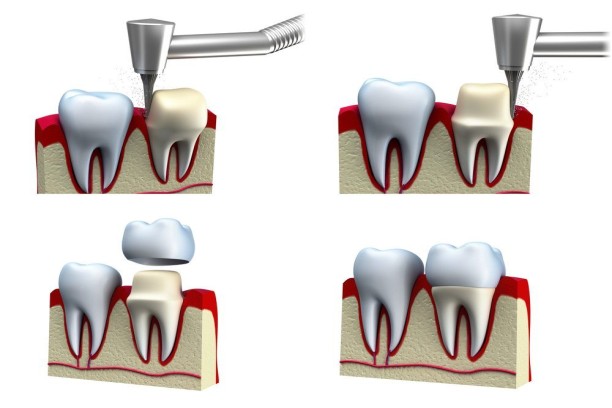

Crown Lengthening

Exposure of more tooth structure for improved restoration and smile appearance.